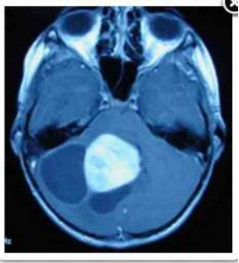

9

Q

In a patient with the MRI shown in the figure, a tumor in what other location would increase the probability of germinoma?

a Frontal lobe

b Suprasellar region

c Fourth ventricle

d Brainstem

e Orbit

A

Suprasellar region